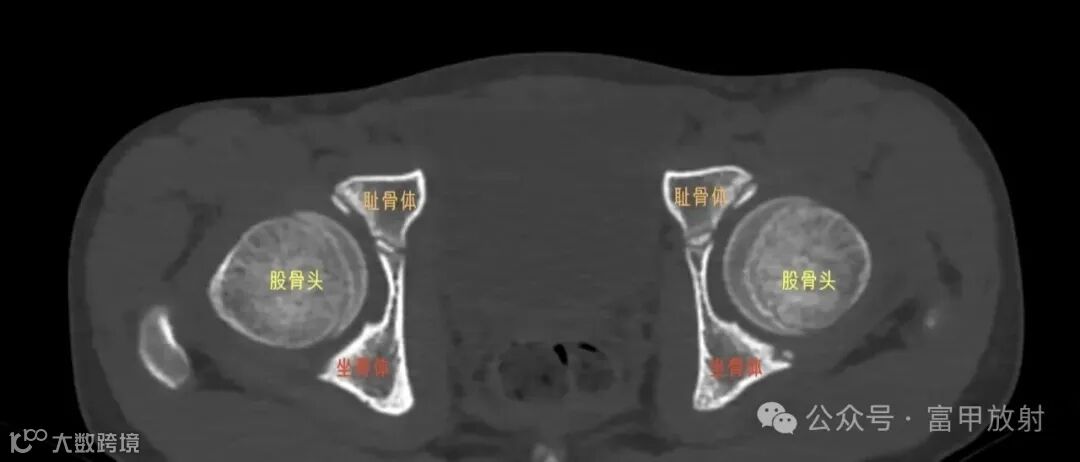

耻骨下支与坐骨分界在哪里?

坐骨结节是坐骨支的突起,是腘绳肌等附着的地方,耻骨结节是耻骨上支内侧缘的突起,腹股沟韧带附着点,在X线上坐骨结节也许估计到,耻骨结节基本上找不到,在这基础上作测量定位置,可靠性会不理想。以下这个简单的方法也许可以帮助到你。